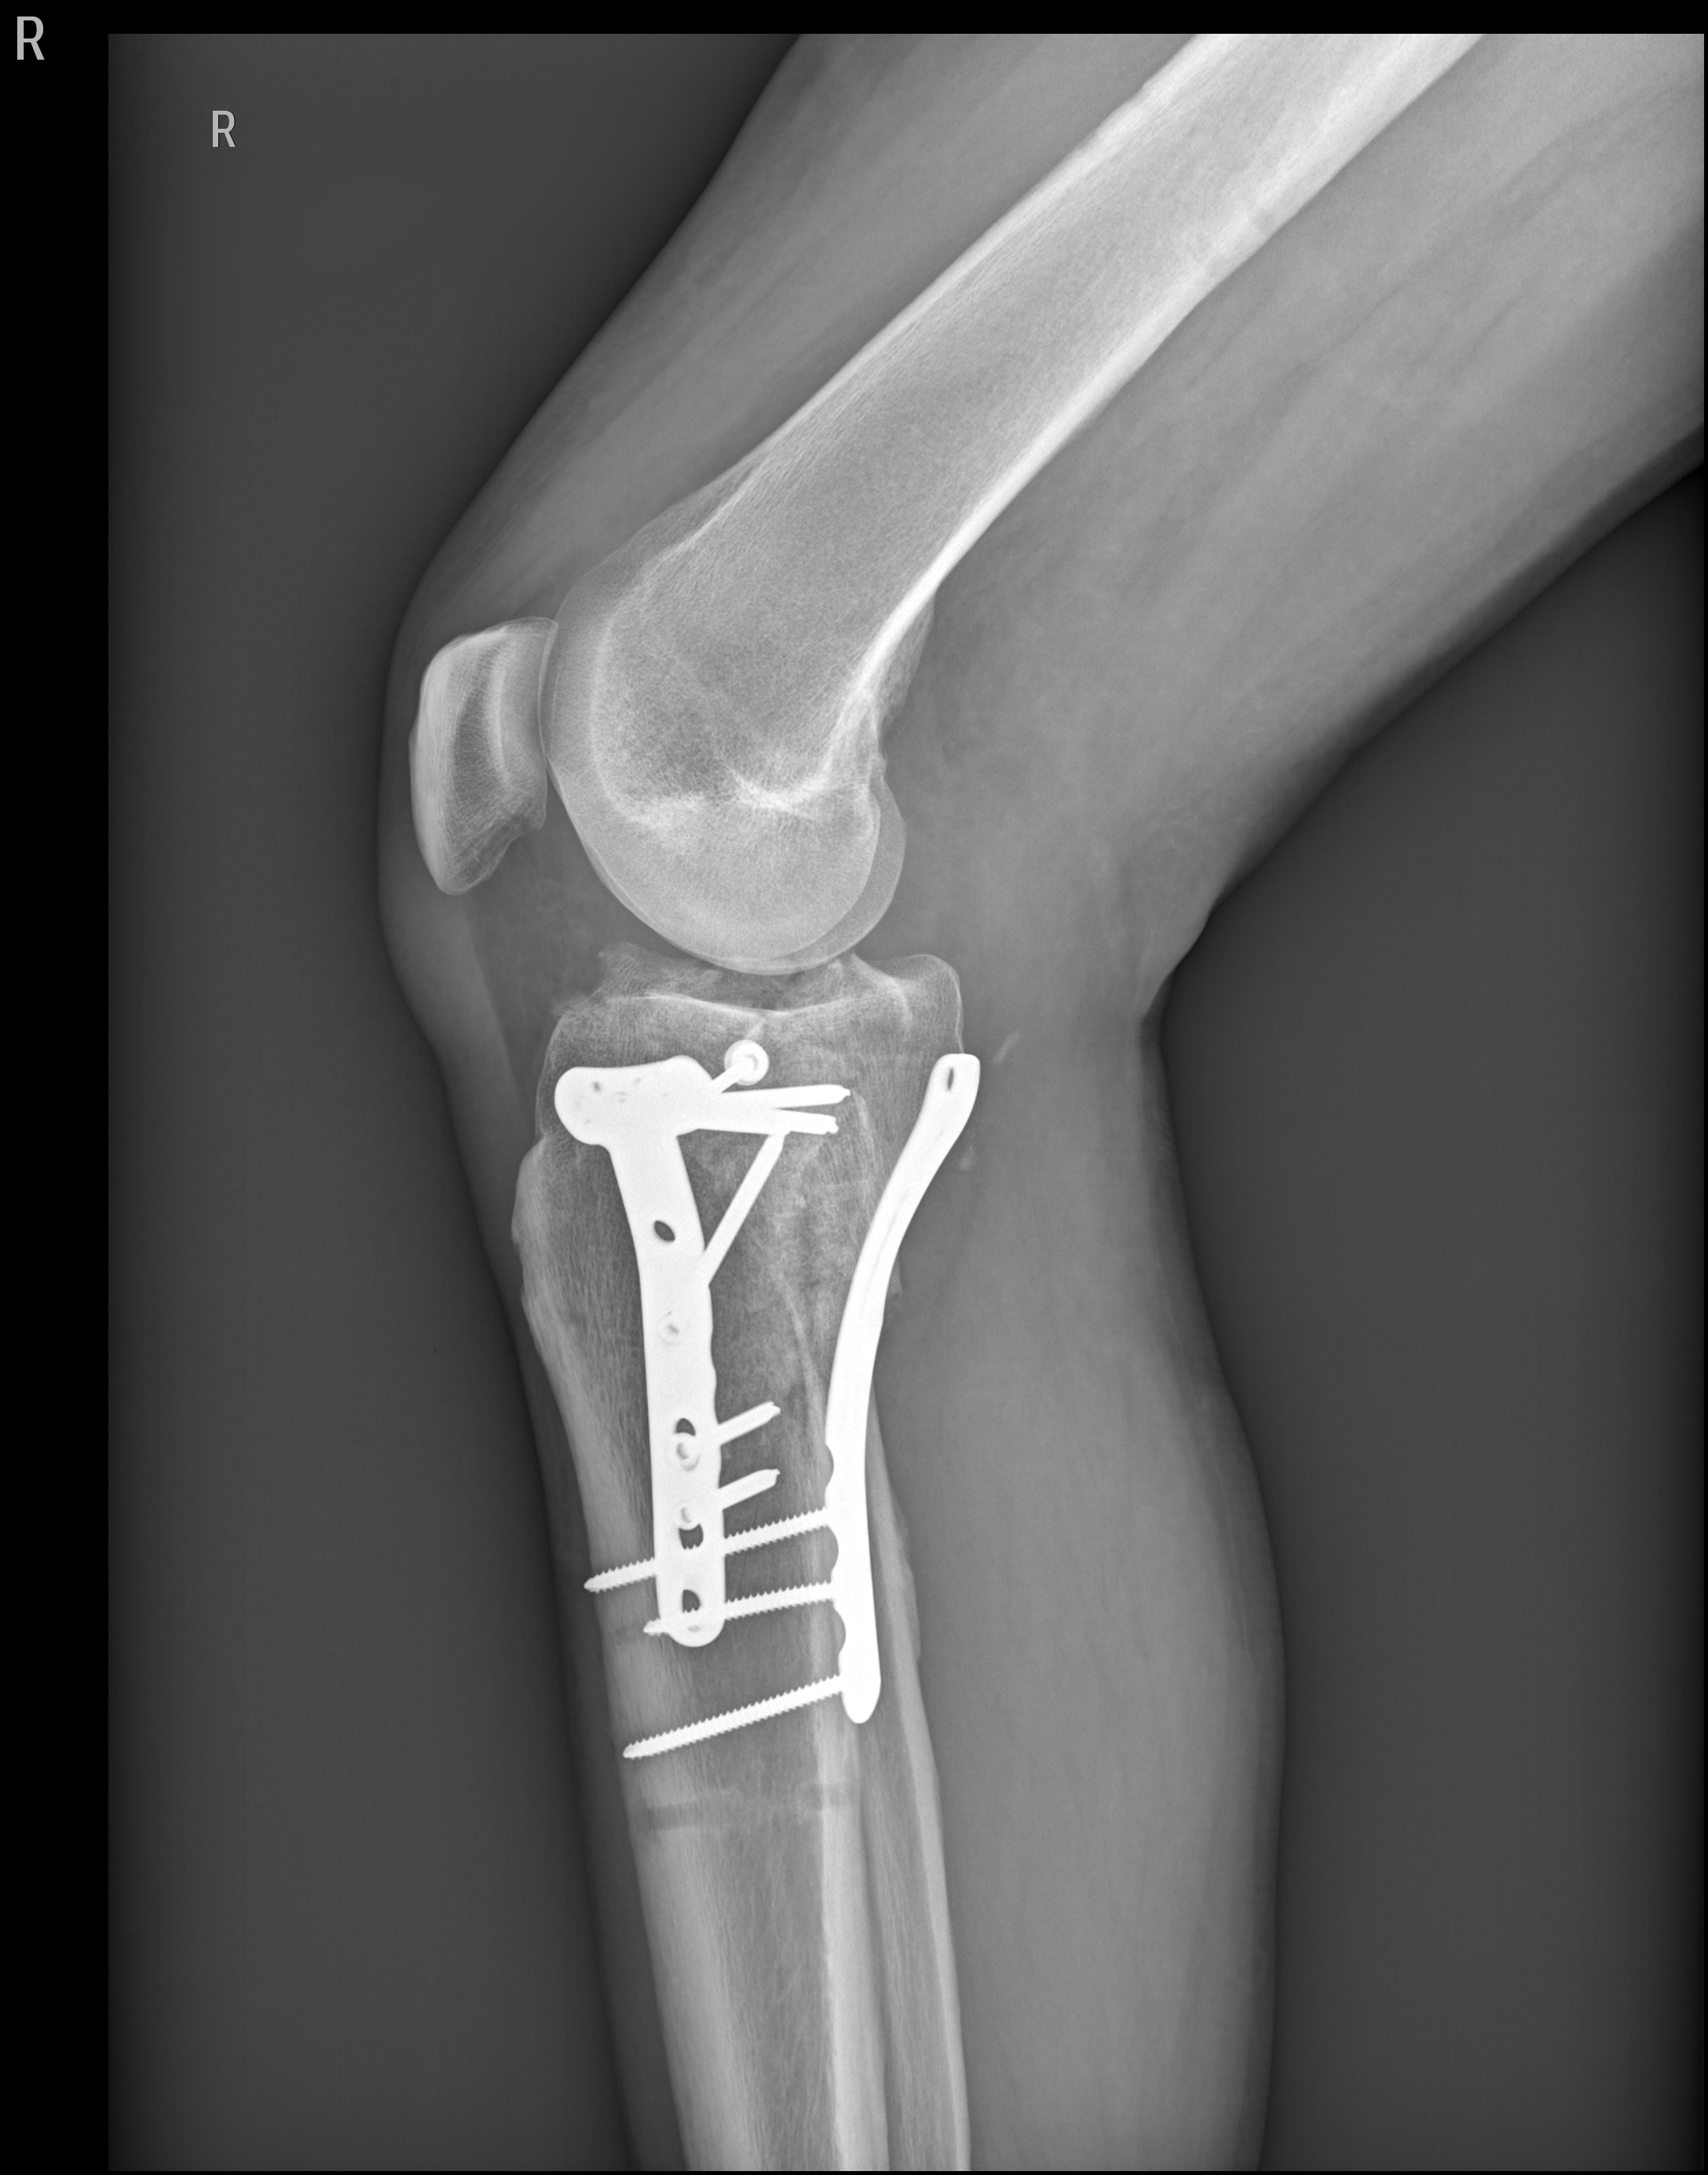

Lange Rede, kurzer Sinn, Schienbein rechts innen durch den Zylinder zerschmettert!

Erstes O.P. Externer Fixateur,

Zweiter O.P.-Bissjen titanium.

Anhang anzeigen 427376

Anhang anzeigen 427377

Die Stangen Aussen - Fixateur extern - fixieren die Fraktur vor bzw. bis zur eigentlichen OP, Schwellung muss runter usw.

Die Schrauben / Plattenosthesynthese fixiert die Fraktur von Innen.

Manches Material entfernt man nach bis zu einem Jahr, manches bleibt dauerhaft drin. Je nach Befund.